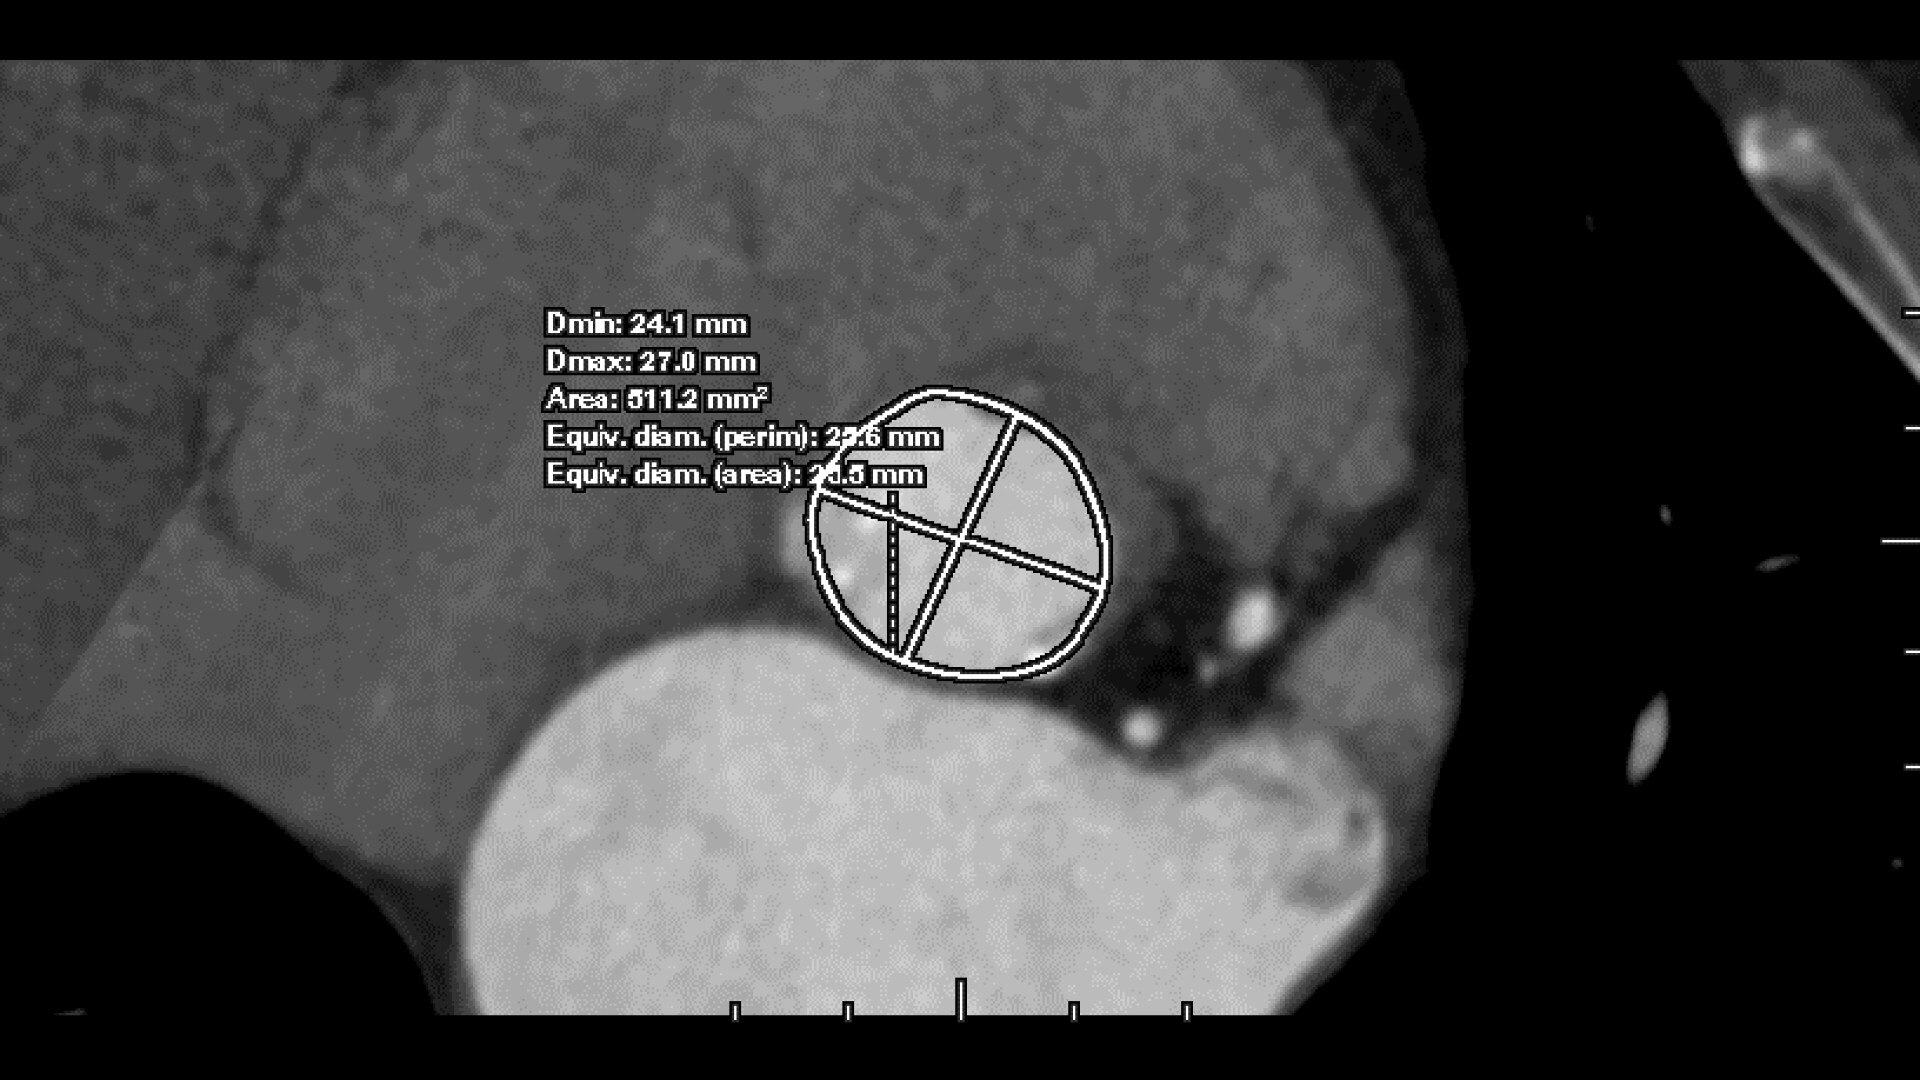

• Automated aortic segmentation and preliminary orientation to aortic annular plane

• 3-point deposit mode for precise refinement of annular plane

• >Faster valve plane detection over a manual method

• Automatic estimate of aortic valve calcium volume measurement